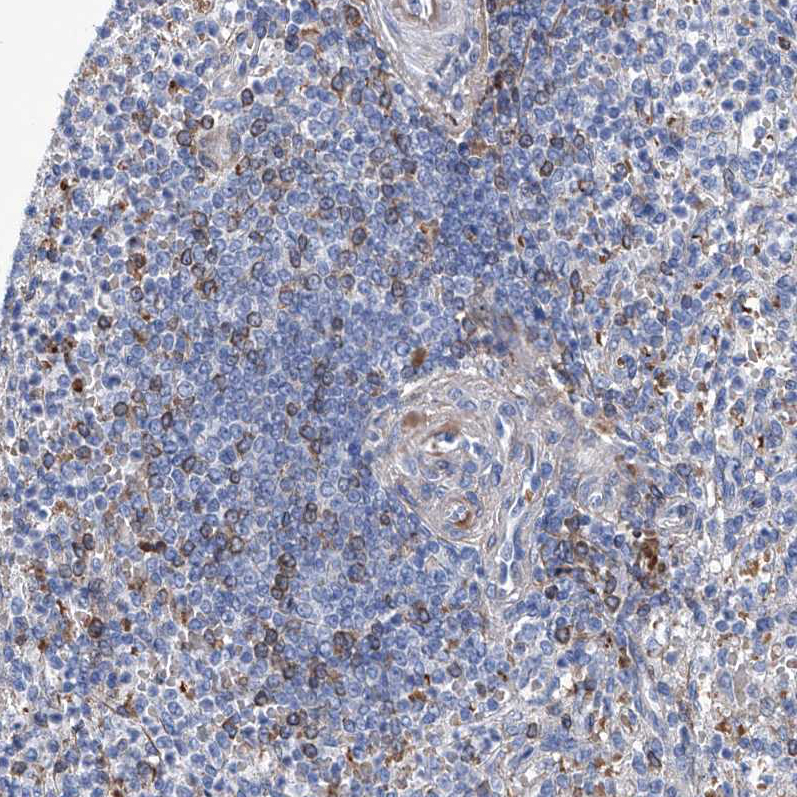

Immunohistochemical staining of human spleen shows moderate membranous positivity in cells in white pulp.